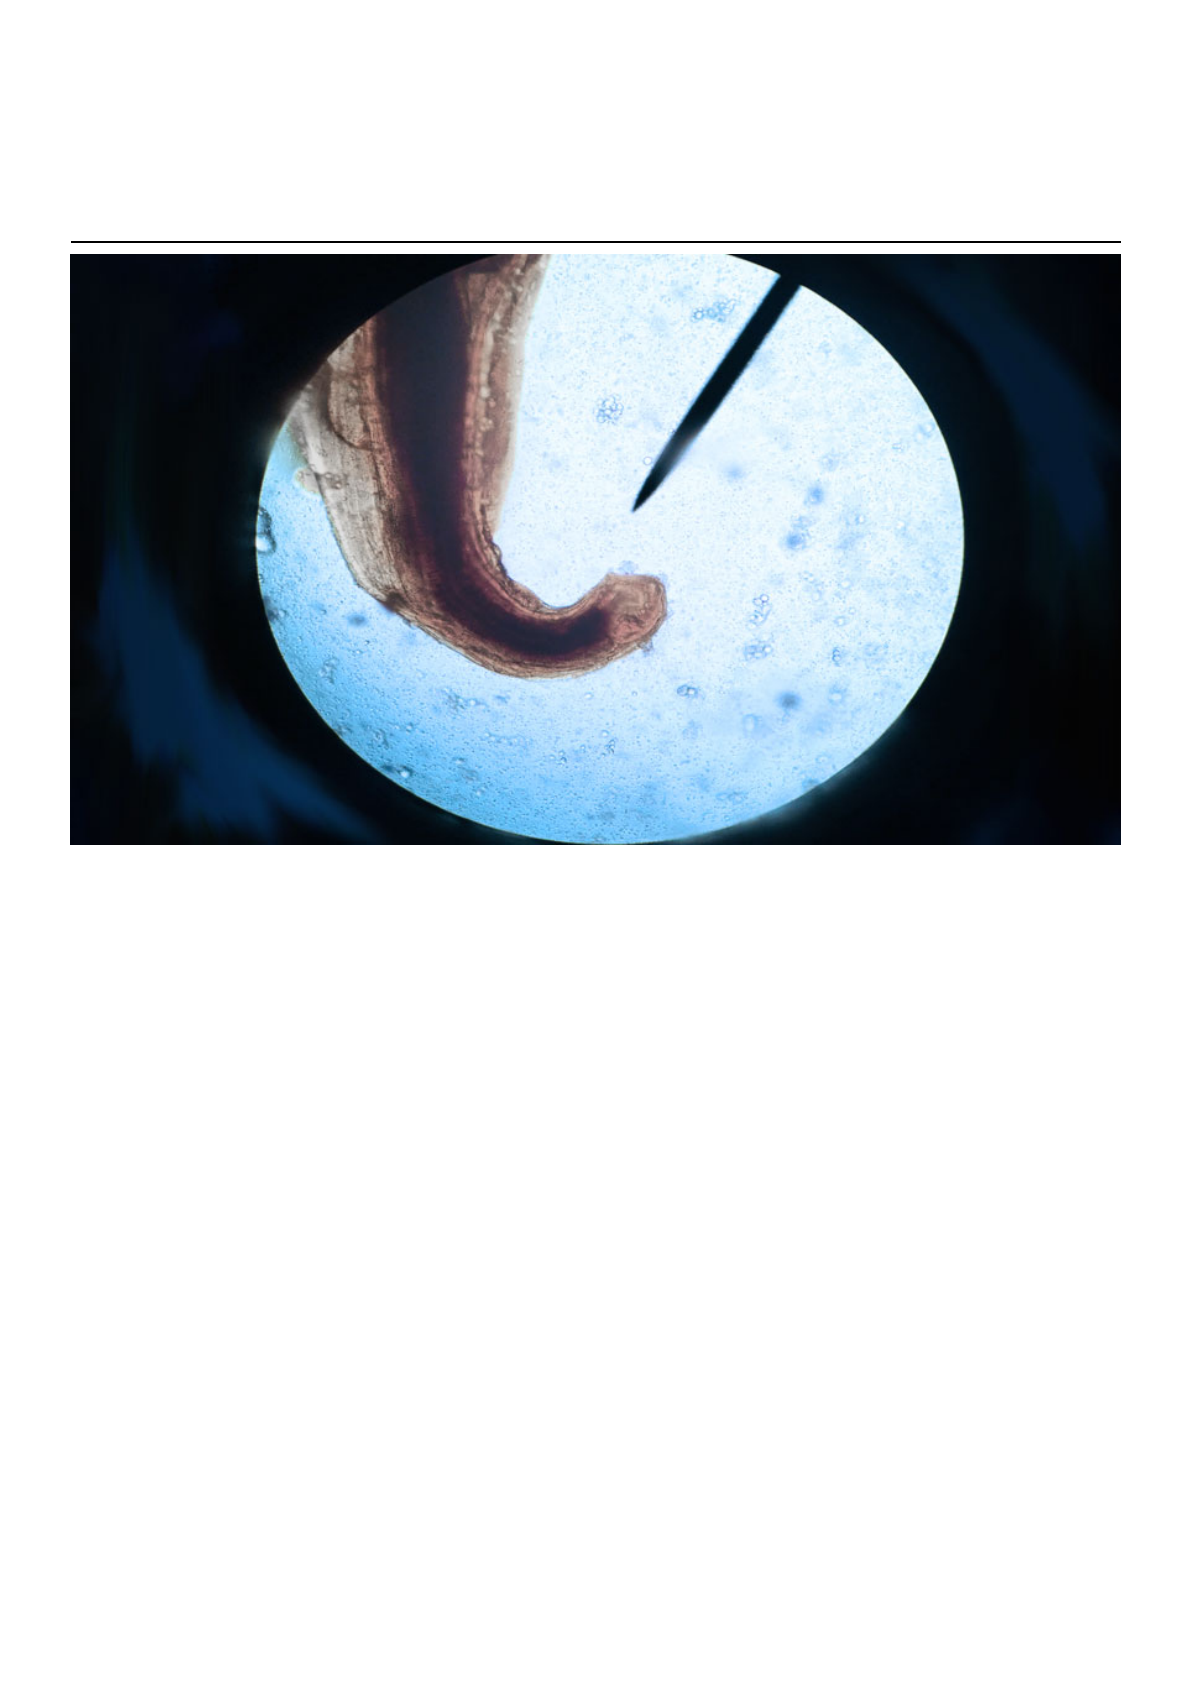

O Ancylostoma duodenale e o Necator americanus são pequenos vermes cilíndricos, que medem entre

0,5 e 1,5 cm de diâmetro e apresentam a cabeça em forma semelhante a um gancho, especialmente o

N. americanus. Ambos apresentam uma boca bem definida, com 2 pares de dentes pontiagudos (A.

duodenale) ou duas placas afiadas (N. americanus), que servem para aderir à parede do intestino e

sugar o sangue do seu hospedeiro.